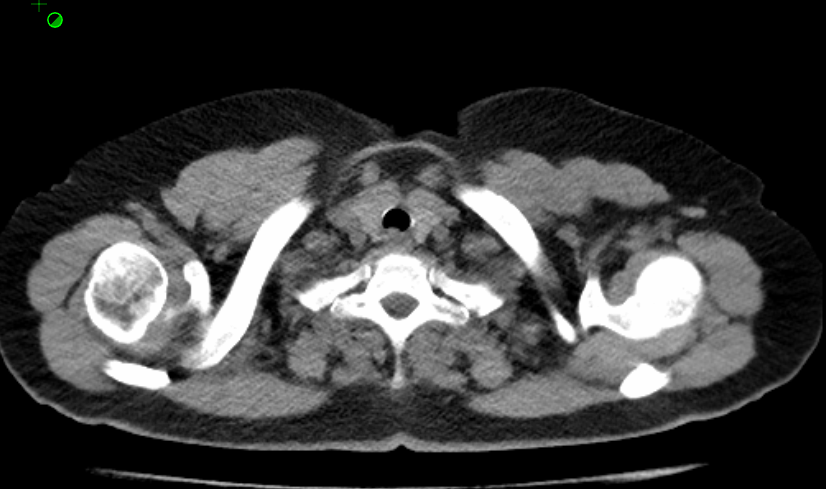

纵隔窗平扫

10月前胸部CT平扫: